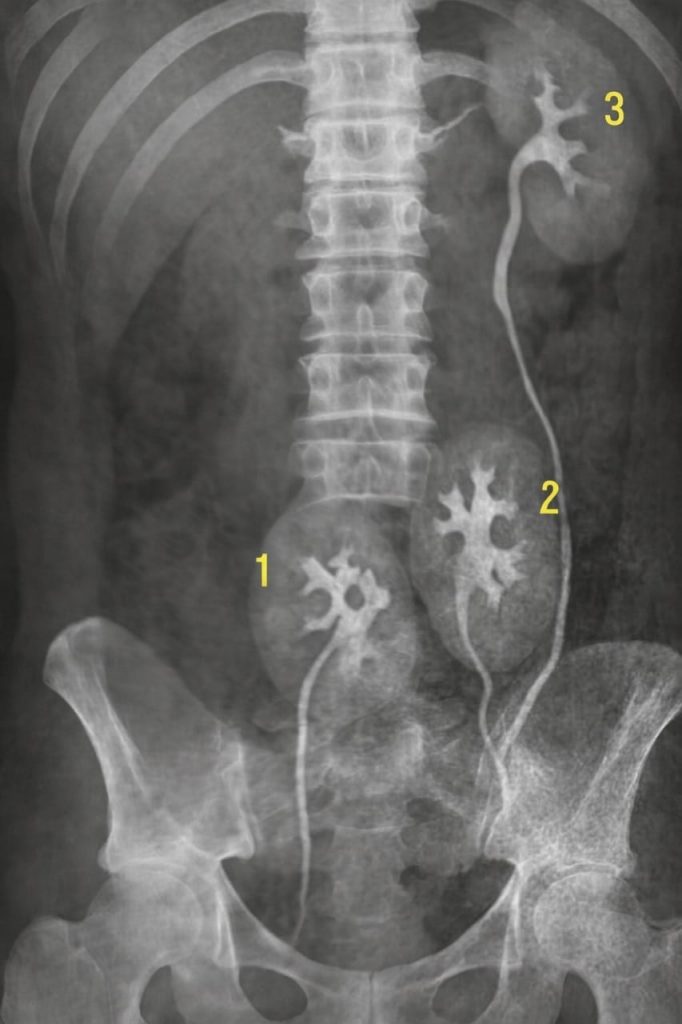

« Regardez », dit le médecin en tournant l’écran. « Voici le contour de votre rein gauche. Tout est normal. »

« Et à droite… » Il esquissa un sourire, comme un homme qui aurait fait une découverte surprenante, mais pas effrayante.

Sur l’écran se dessinaient deux silhouettes distinctes. Deux organes côte à côte, comme deux feuilles soudées.

« Non. Ce sont deux reins. Et les deux sont fonctionnels. »

« On appelle cela un “rein accessoire”. C’est un cas très rare. On en a recensé moins d’une centaine depuis que nous l’observons. Généralement, cela ne se manifeste d’aucune façon… comme chez vous. » « Et moi… je ne cours aucun danger ? »